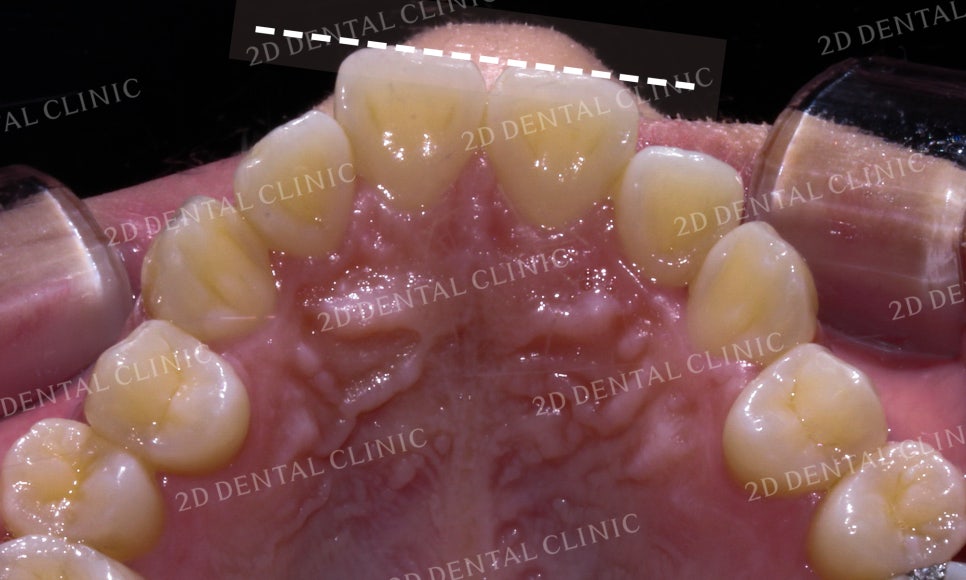

전치부의 전체적인 치아들을 봤을 때 역시

정밀검진 시 발견되었던 총생이 있는

모습입니다.

특히 측절치와 견치가 설측으로

과하게 들어와 있는 모습이네요.

상악의 설측면 사진입니다.

역시 중절치를 비롯한 전치부의 치아에서

전체적으로 크라우딩이 발견되고 있습니다.

*구치부의 치아는 교정을 진행하지 않은 Case입니다.